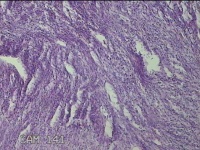

子宫肌瘤结节

多发性子宫肌瘤 继发性不孕症 子宫Ⅰ度脱垂 高脂血症 胆囊息肉

一般病史

发现子宫肌瘤4年余,继发不孕3年。

标本名称

大体所见

灰白暗红色圆形肿物10x9x2.8㎝九个,表面糜烂,切面均为灰白色结节状或编织状,质中。